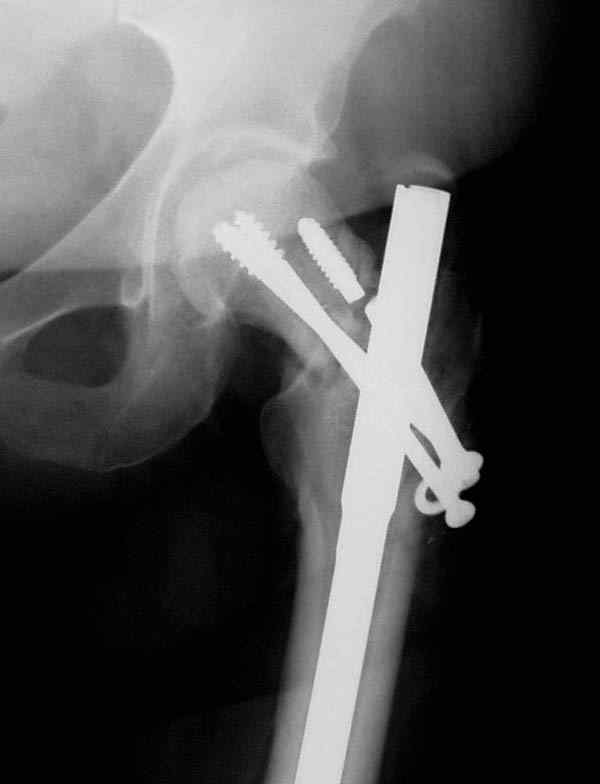

Учитывая молодой возраст больного, из всех рекомендуемых вариантов для лечения ложного сустава шейки предпочтительным является вальгусная остеотомия (на сайте имеются прежние разборы) из-за простоты исполнения и биомехнических преимуществ.

Несмотря на пессимистические прогнозы, у молодых

коррегирующая вальгусная остеотомия является более

приемлемым.

Представленные случаи доказательства тому, что еще

имеется резервы на восстановление даже у 5-6 месячных ложных суставов шейки.